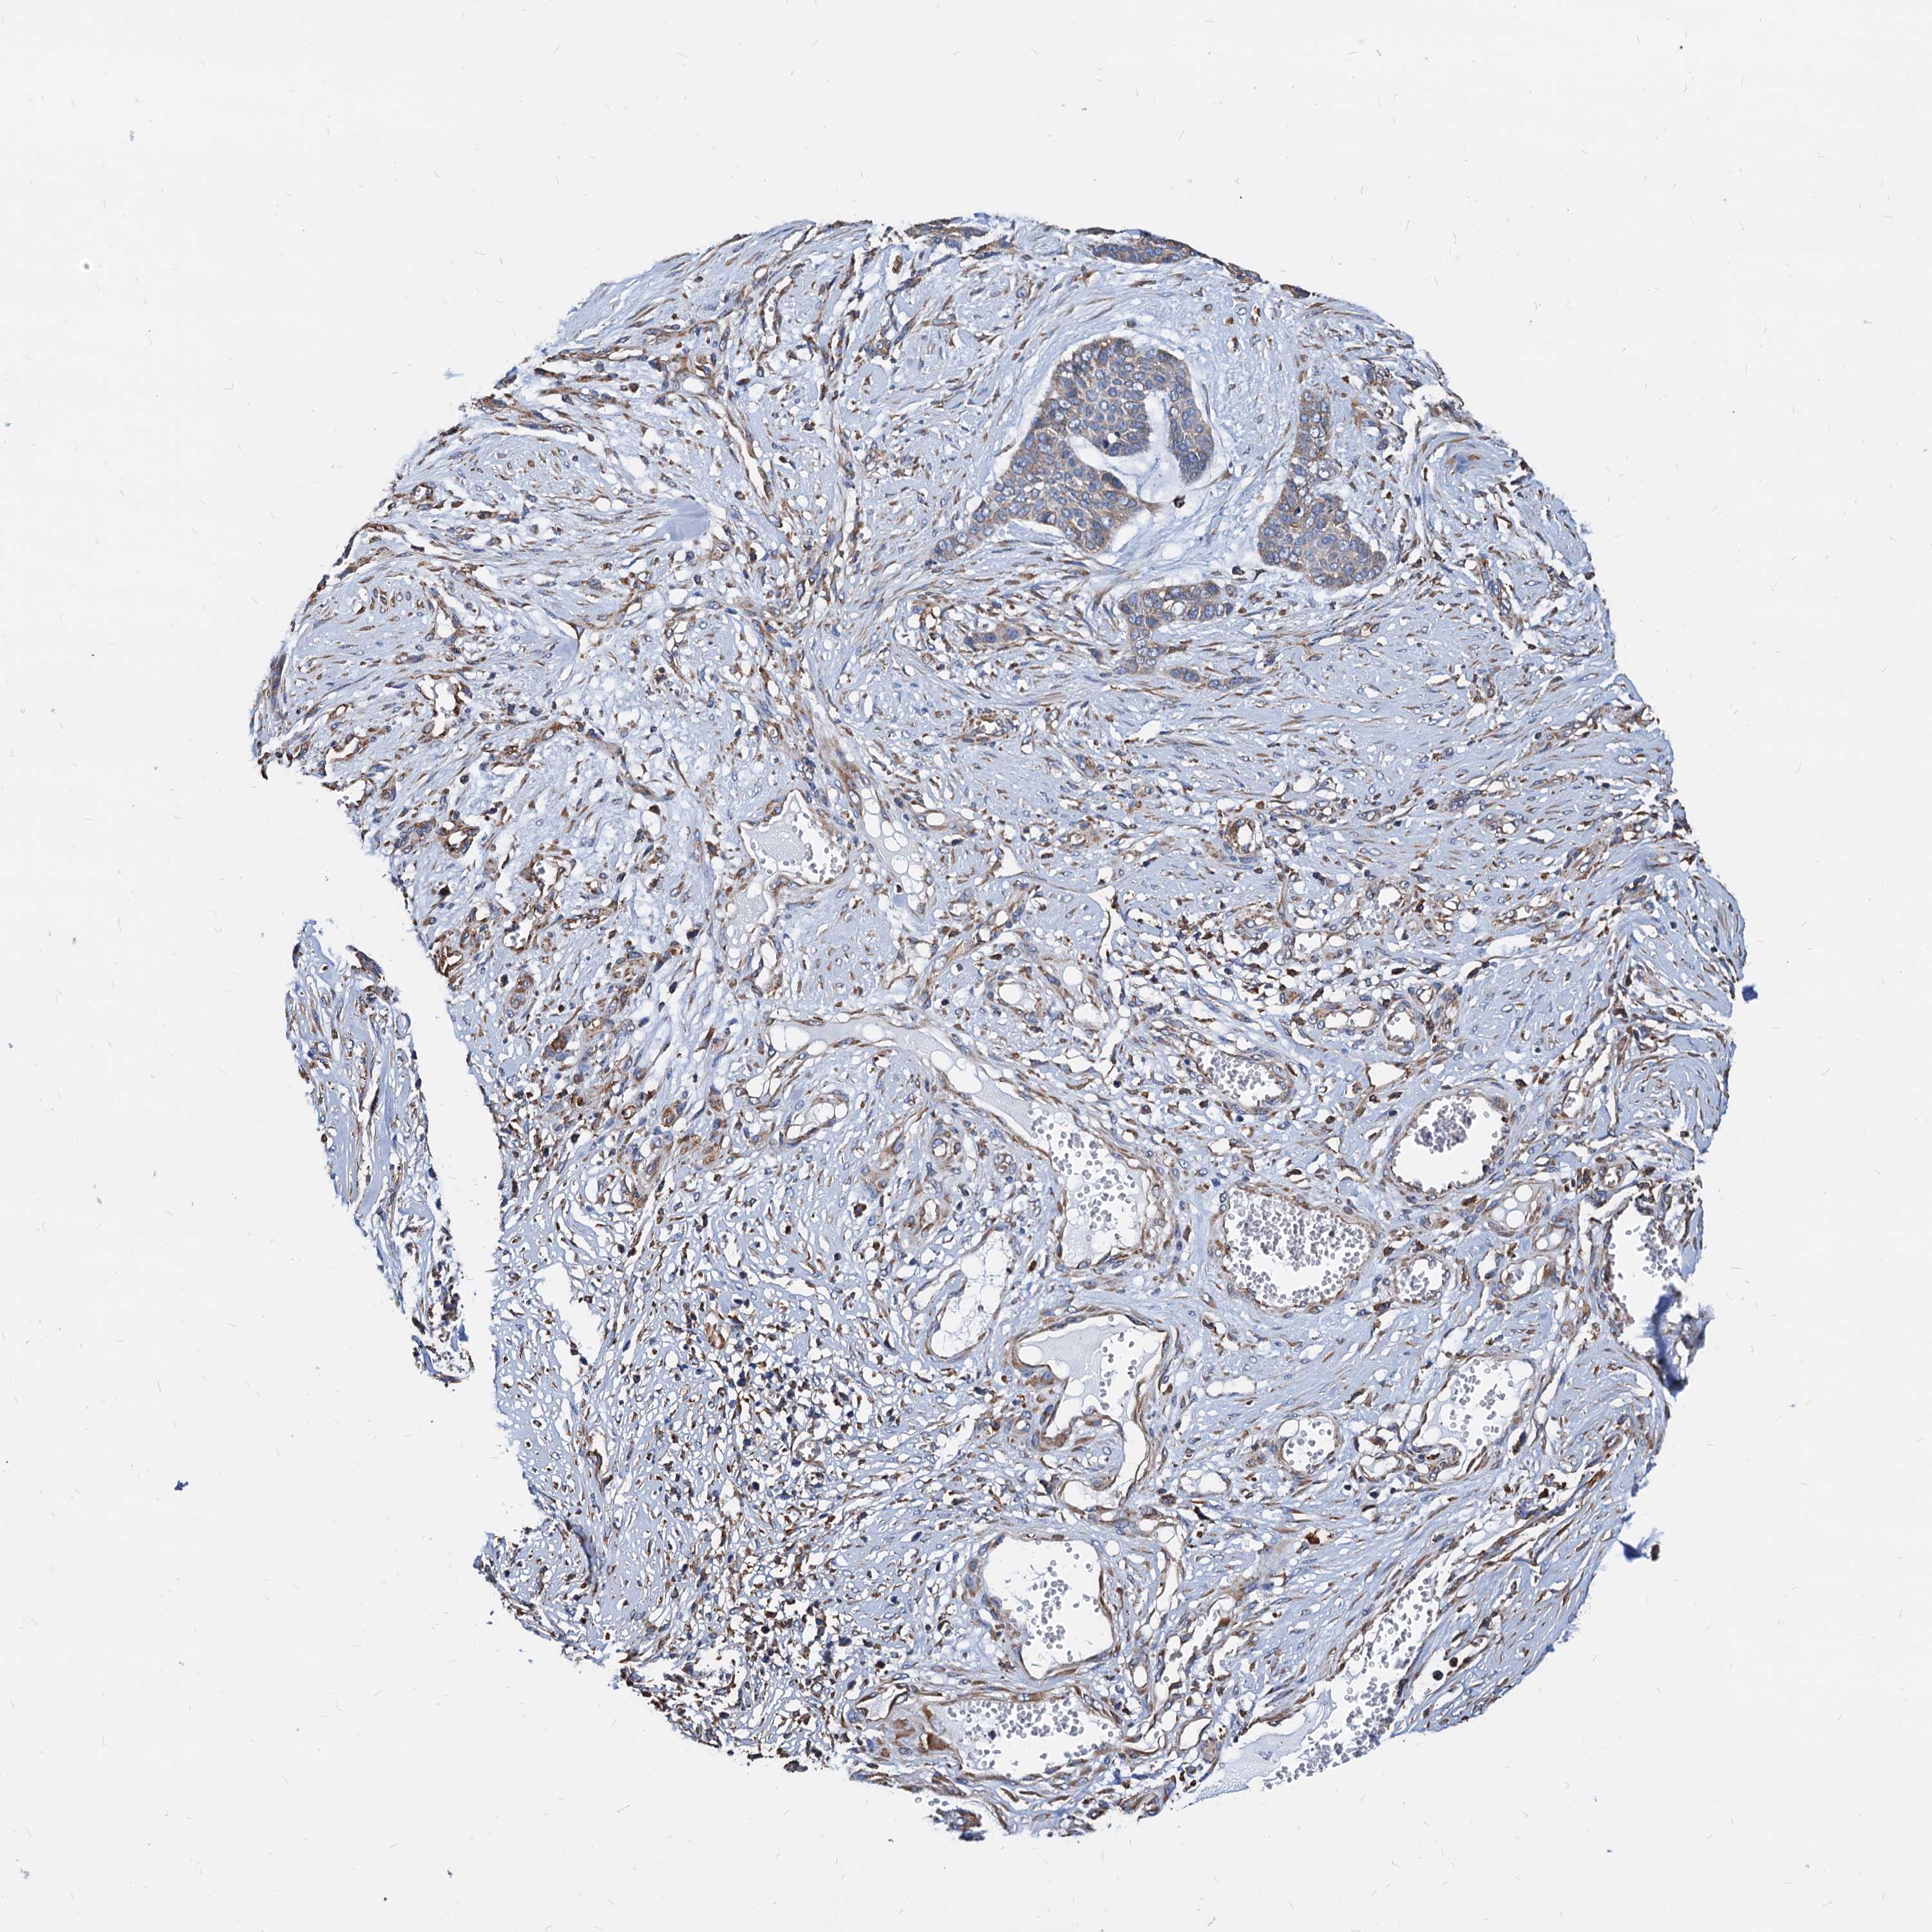

SKIN CANCER - Protein expressioni

A mouse-over function shows sample information and annotation data. Click on an image to view it in a full screen mode. Samples can be filtered based on level of antibody staining by selecting one or several of the following categories: high, medium, low and not detected. The assay and annotation is described here.

Each image is clickable and will lead to virtual microscopy that enables deeper exploration of all samples and also displays staining intensity scores, fraction scores and subcellular localization as well as patient and tissue information for each sample.

Antibody HPA038846

Staining

Low

Weak

75%-25%

Cytoplasmic/membranous

Squamous cell carcinoma, NOS